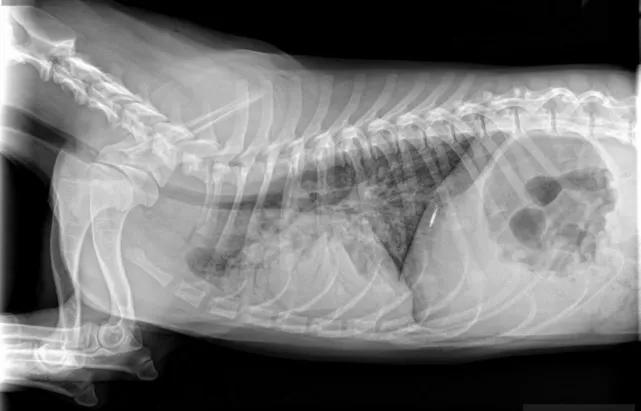

胃肠梗阻

肠胃梗阻包括胃扭转、肠套叠、肠梗阻等一系列胃肠道阻塞疾病,尤其是喂了鸡骨头、误食玩具、刚吃完饭运动等情况最容易发生。

肠梗阻一般都会伴发呕吐和腹泻,有的还会便血。在初期狗狗会表现食欲不振,甚至干脆不吃不喝。该病属于危重疾病,往往都表现出几天内不进食,最终快速死亡。

如果你家的狗狗,好几天不爱吃饭,但没有呕吐拉稀等症状,可以不考虑这些疾病。如果有上述提及的症状和描述,要格外小心,特别需要注意喂食过尖锐的骨头、或者有啃咬硬质玩具习惯的狗狗。

医院检查这些疾病,X光片最常见,每次需要拍摄正侧位两张,价格240元左右。也可能涉及腹部超声,价格100~200元。